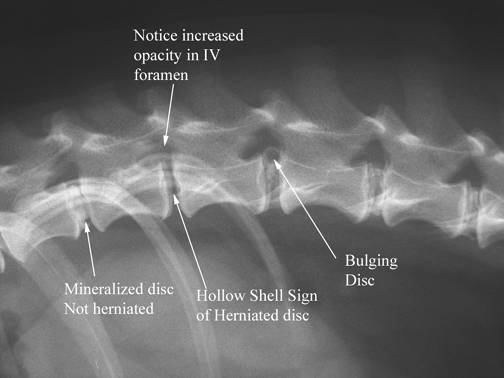

Product code: Degenerative disc disease discount in dogs

Degenerative disc disease discount in dogs